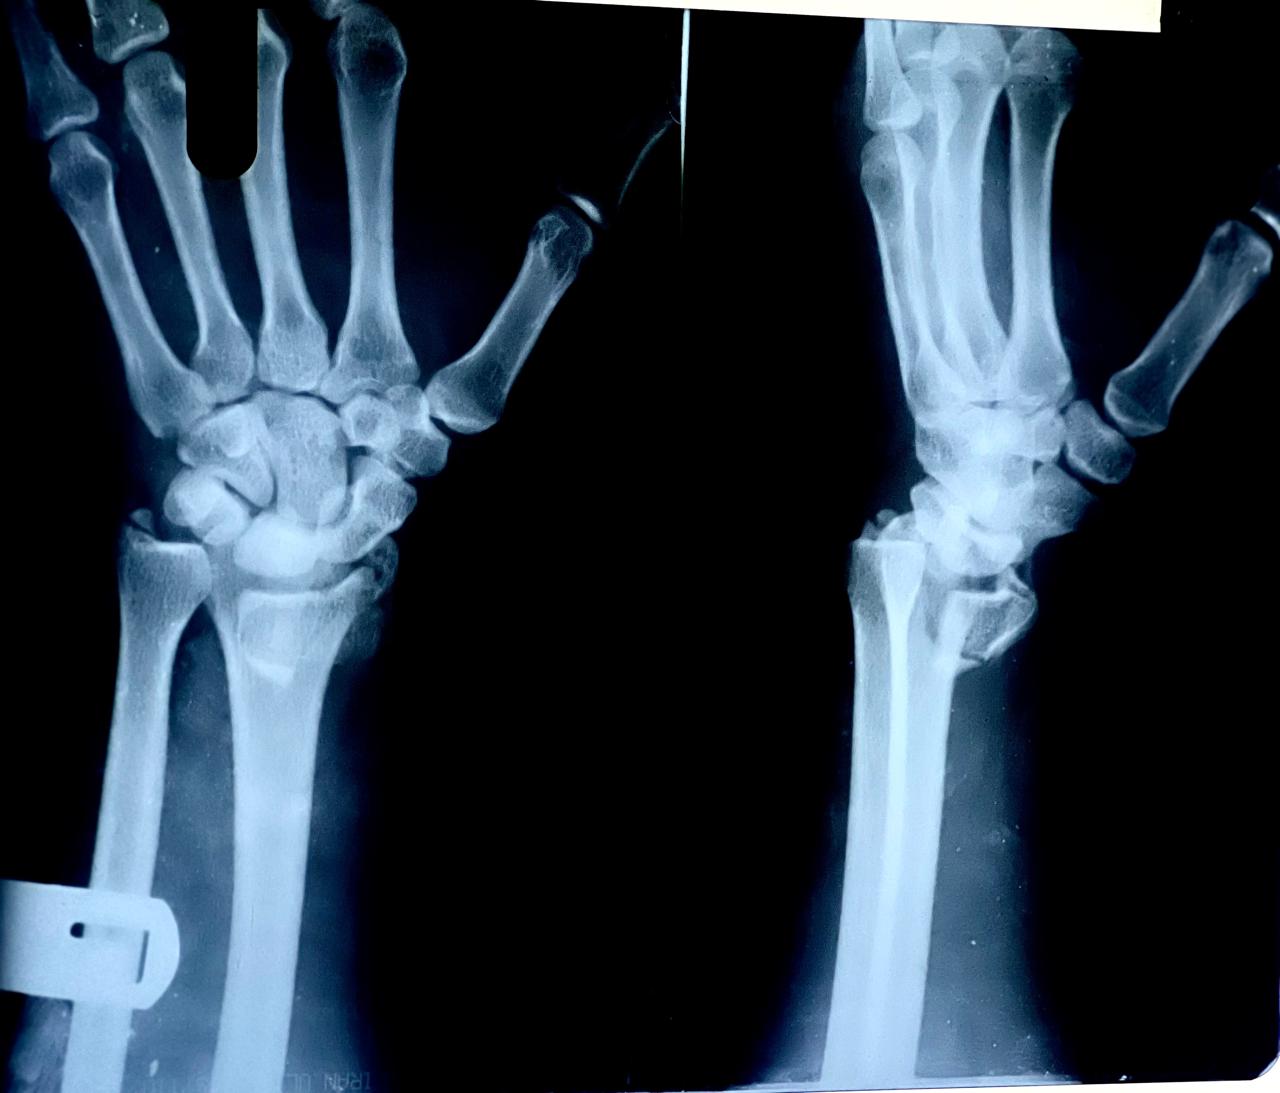

Pre-Operative X-ray

• Displaced distal radius fracture

• Loss of normal anatomical alignment

• No joint surface involvement

Post-Operative X-ray Findings

• Anatomical reduction achieved

• Correct placement of plate and screws

• Strong and stable fixation